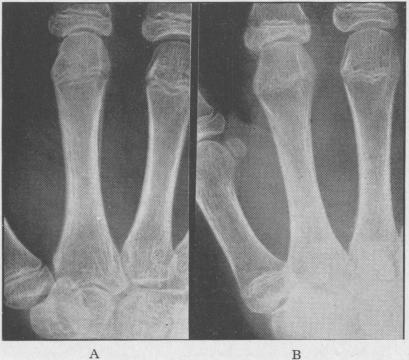

Juvenile rheumatoid arthritis (Still's disease).